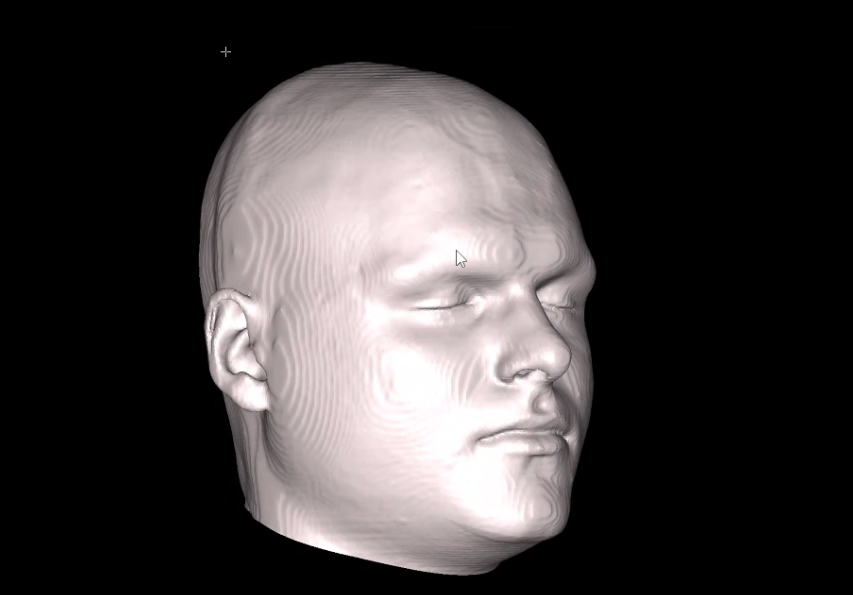

Here is how my side profile looks IRL:

Here is how my side profile looks IRL: